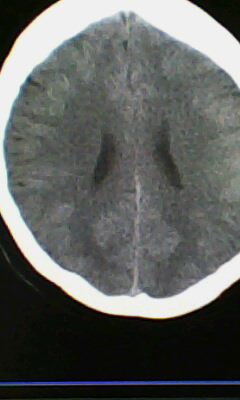

标题: CT25171:患者间断性头痛 无外伤史 [打印本页]

标题: CT25171:患者间断性头痛 无外伤史

右侧额叶脑穿通畸形囊肿。

图不清,有灰质异位吗?与脑裂畸形鉴别

右侧额叶脑穿通畸形囊肿。支持!